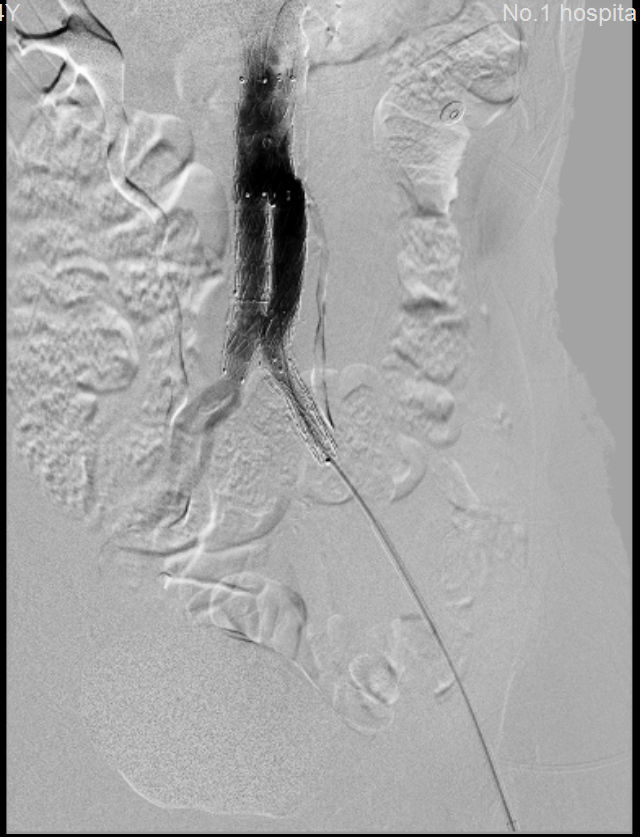

術(shù)前 術(shù)后